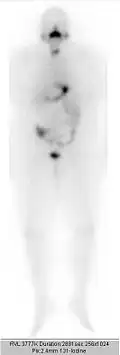

Scintigraphie corps entier après une 1re radiothérapie ablative avec 3,7 GBq de 131I. Stockage intensif dans le reste de la thyroïde.

…après une 2e radiothérapie ablative avec 3,7 GBq de 131I. Faible stockage dans le reste de la thyroïde.

…après une 2e radiothérapie ablative avec 3,7 GBq de 131I. Stockage minimal dans le reste de la thyroïde.

Scintigraphie corps entier : test à 131I (370 MBq). Activité physiologique : glandes salivaires, estomac, intestin et vessie. Pas de stockage dans la thyroïde.

Quelques jours après la radiothérapie, on fait une scintigraphie du corps entier. La thérapie sera répétée à des intervalles d'environ 3 mois, jusqu'à ce que ni la scintigraphie, ni l'échographie du cou, ni le marqueur de tumeur thyroglobuline n'indiquent la présence de tissu thyroïdien résiduel (malin ou bénin). Une activité totale pour tous les traitements de radiothérapie jusqu'à 75 GBq (2 000 mCi) est usuellement supportée sans problème par des patients autrement sains. Pour des activités supérieures, il faut envisager un risque de dommages durables à la moelle osseuse fabriquant les cellules sanguines.